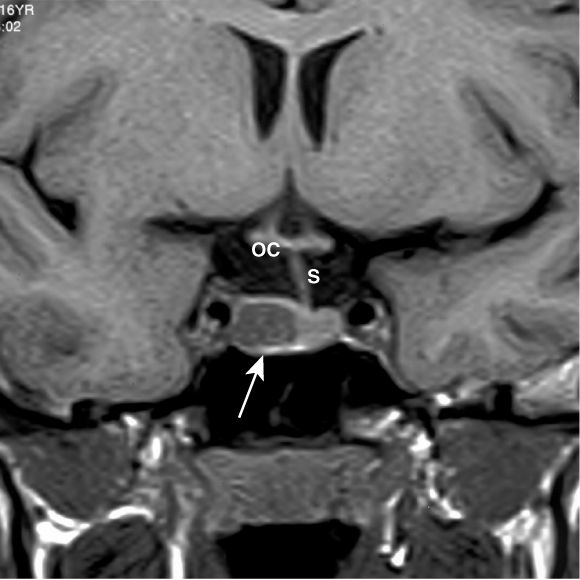

Management: An MRI scan (coronal view above) showed a 1 cm mass of low signal intensity within the right lobe of the pituitary gland (arrow), displacing the pituitary stalk to the left, characteristic of a small prolactinoma. Optic chiasm is labelled OC.